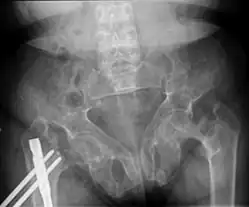

Renal osteodystrophy is usually diagnosed after treatment for end-stage kidney disease begins; however the CKD-MBD starts early in the course of CKD.[1][6] In advanced stages, blood tests will indicate decreased calcium and calcitriol (vitamin D) and increased phosphate, and parathyroid hormone levels. In earlier stages, serum calcium, phosphate levels are normal at the expense of high parathyroid hormone and fibroblast growth factor-23 levels. X-rays will also show bone features of renal osteodystrophy (subperiostic bone resorption, chondrocalcinosis at the knees and pubic symphysis, osteopenia and bone fractures) but may be difficult to differentiate from other conditions. Since the diagnosis of these bone abnormalities cannot be obtained correctly by clinical, biochemical, and imaging methods (including measurement of bone-mineral density), bone biopsy has been, and still remains, the gold standard analysis for assessing the exact type of renal osteodystrophy.[6][16]

Brown tumors in the pelvis and a hip fracture.[18] -